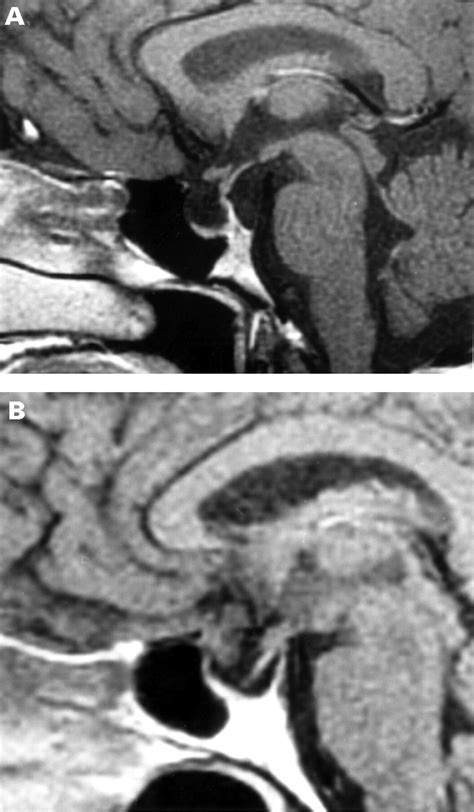

To understand this condition, we must first look at the sella turcica—a bony, saddle-shaped depression at the base of the skull that houses and protects the pituitary gland. In a typical anatomy, the sella is filled primarily by the pituitary gland itself. However, in individuals with an Empty Sella Syndrome (ESS), the sella appears "empty" on imaging results like an MRI or CT scan because it has become filled with cerebrospinal fluid (CSF).

When the condition is classified as a Partial Empty Sella, it means that the sella is only partially filled with CSF, while a significant portion of the pituitary gland remains in its expected position. This can occur due to a defect in the diaphragm sellae—the fold of dura mater that usually acts as a barrier between the brain and the pituitary gland. If this seal is weak, the increased pressure of the CSF can push into the sella, flattening the gland against the bony walls.

Medical professionals generally categorize this condition into two types: primary and secondary. Understanding the distinction is crucial for determining the appropriate diagnostic pathway.

• Primary Partial Empty Sella: This is often congenital or related to increased intracranial pressure. It is frequently seen in individuals who are obese, have hypertension, or in women of middle age.

• Secondary Partial Empty Sella: This occurs due to an underlying event, such as a previously removed pituitary tumor, radiation therapy, or an injury to the base of the skull.